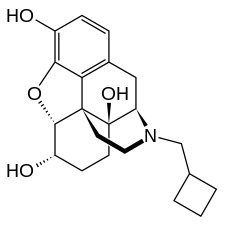

Opioid antagonists

- Methylnaltrexone (Methylnaltrexone is only peripherally active as it does not cross the blood–brain barrier in sufficient quantities to be centrally active. As such, it can be considered the antithesis of loperamide.)

- Naloxegol (Naloxegol is only peripherally active as it does not cross the blood–brain barrier in sufficient quantities to be centrally active. As such, it can be considered the antitheses of loperamide.)